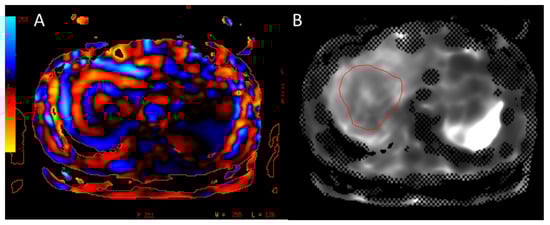

- Mizuno, M.; Tago, K.; Okada, M.; Nakazawa, Y.; Arakane, T.; Yoshikawa, H.; Abe, H.; Matsumoto, N.; Higaki, T.; Okamura, Y.; et al. Extracellular volume by dual energy CT, hepatic reserve capacity scoring, CT. volumetry and Transient-elastographyfor estimating liver fibrosis. Sci. Rep. 2023, 13, 22038. [Google Scholar] [CrossRef]

- Arakane, T.; Okada, M.; Nakazawa, Y.; Tago, K.; Yoshikawa, H.; Mizuno, M.; Abe, H.; Higaki, H.; Okamura, Y.; Takayama, T. Comparison between intravoxel incoherent motion and splenic volumetry to predict hepatic fibrosis staging in preoperative patients. Diagnostics 2023, 13, 3200. [Google Scholar] [CrossRef]

- Nakazawa, Y.; Okada, M.; Tago, K.; Kuwabara, N.; Mizuno, M.; Abe, H.; Higaki, T.; Okamura, Y.; Takayama, T. Comparison between MR elastography and combination of CT, Gd-EOB-DTPAenhanced MRI and type IV collagen 7S for estimation of severe liver fibrosis in preoperative patients with hepatobiliary tumors. Eur. Radiol. 2024; Online ahead of print. [Google Scholar] [CrossRef]